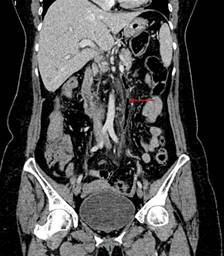

En el caso presentado, se observan datos de diverticulitis complicada a nivel de colon sigmoides, con trombo aéreo en vena sigmoidea adyacente y con extensión a vena mesentérica inferior (Figuras 1 y 2). Además, se visualiza defecto de llenado de la vena porta izquierda, secundario a trombo (Figura 3).

Figura 2: Tomografía computarizada de abdomen en plano coronal, fase venosa temprana. Se visualiza trombo aéreo intraluminal en la vena mesentérica inferior (flecha roja), acompañada de estriación grasa en todo su trayecto (datos de flebitis).